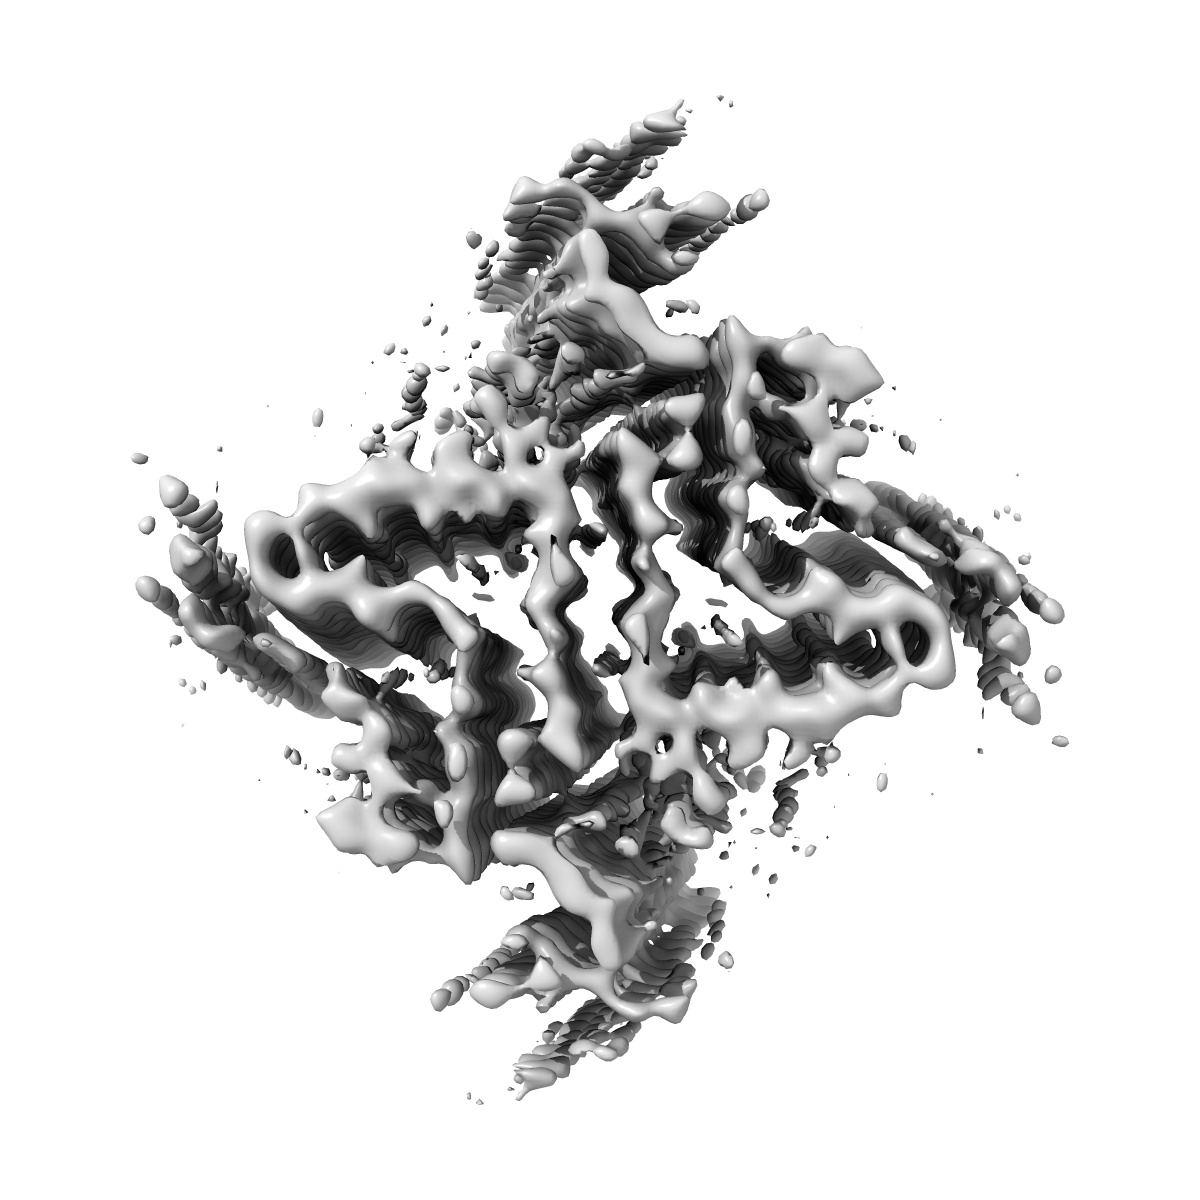

Structure of amplified aSyn filament by using seed amplification assay (SAA) from MSA patient CSF.

Helical reconstruction3.9 Å

Sample: Alpha-synuclein protein filament

Seed amplification of MSA alpha-synuclein aggregates preserves the biological and structural properties of brain-derived aggregates.